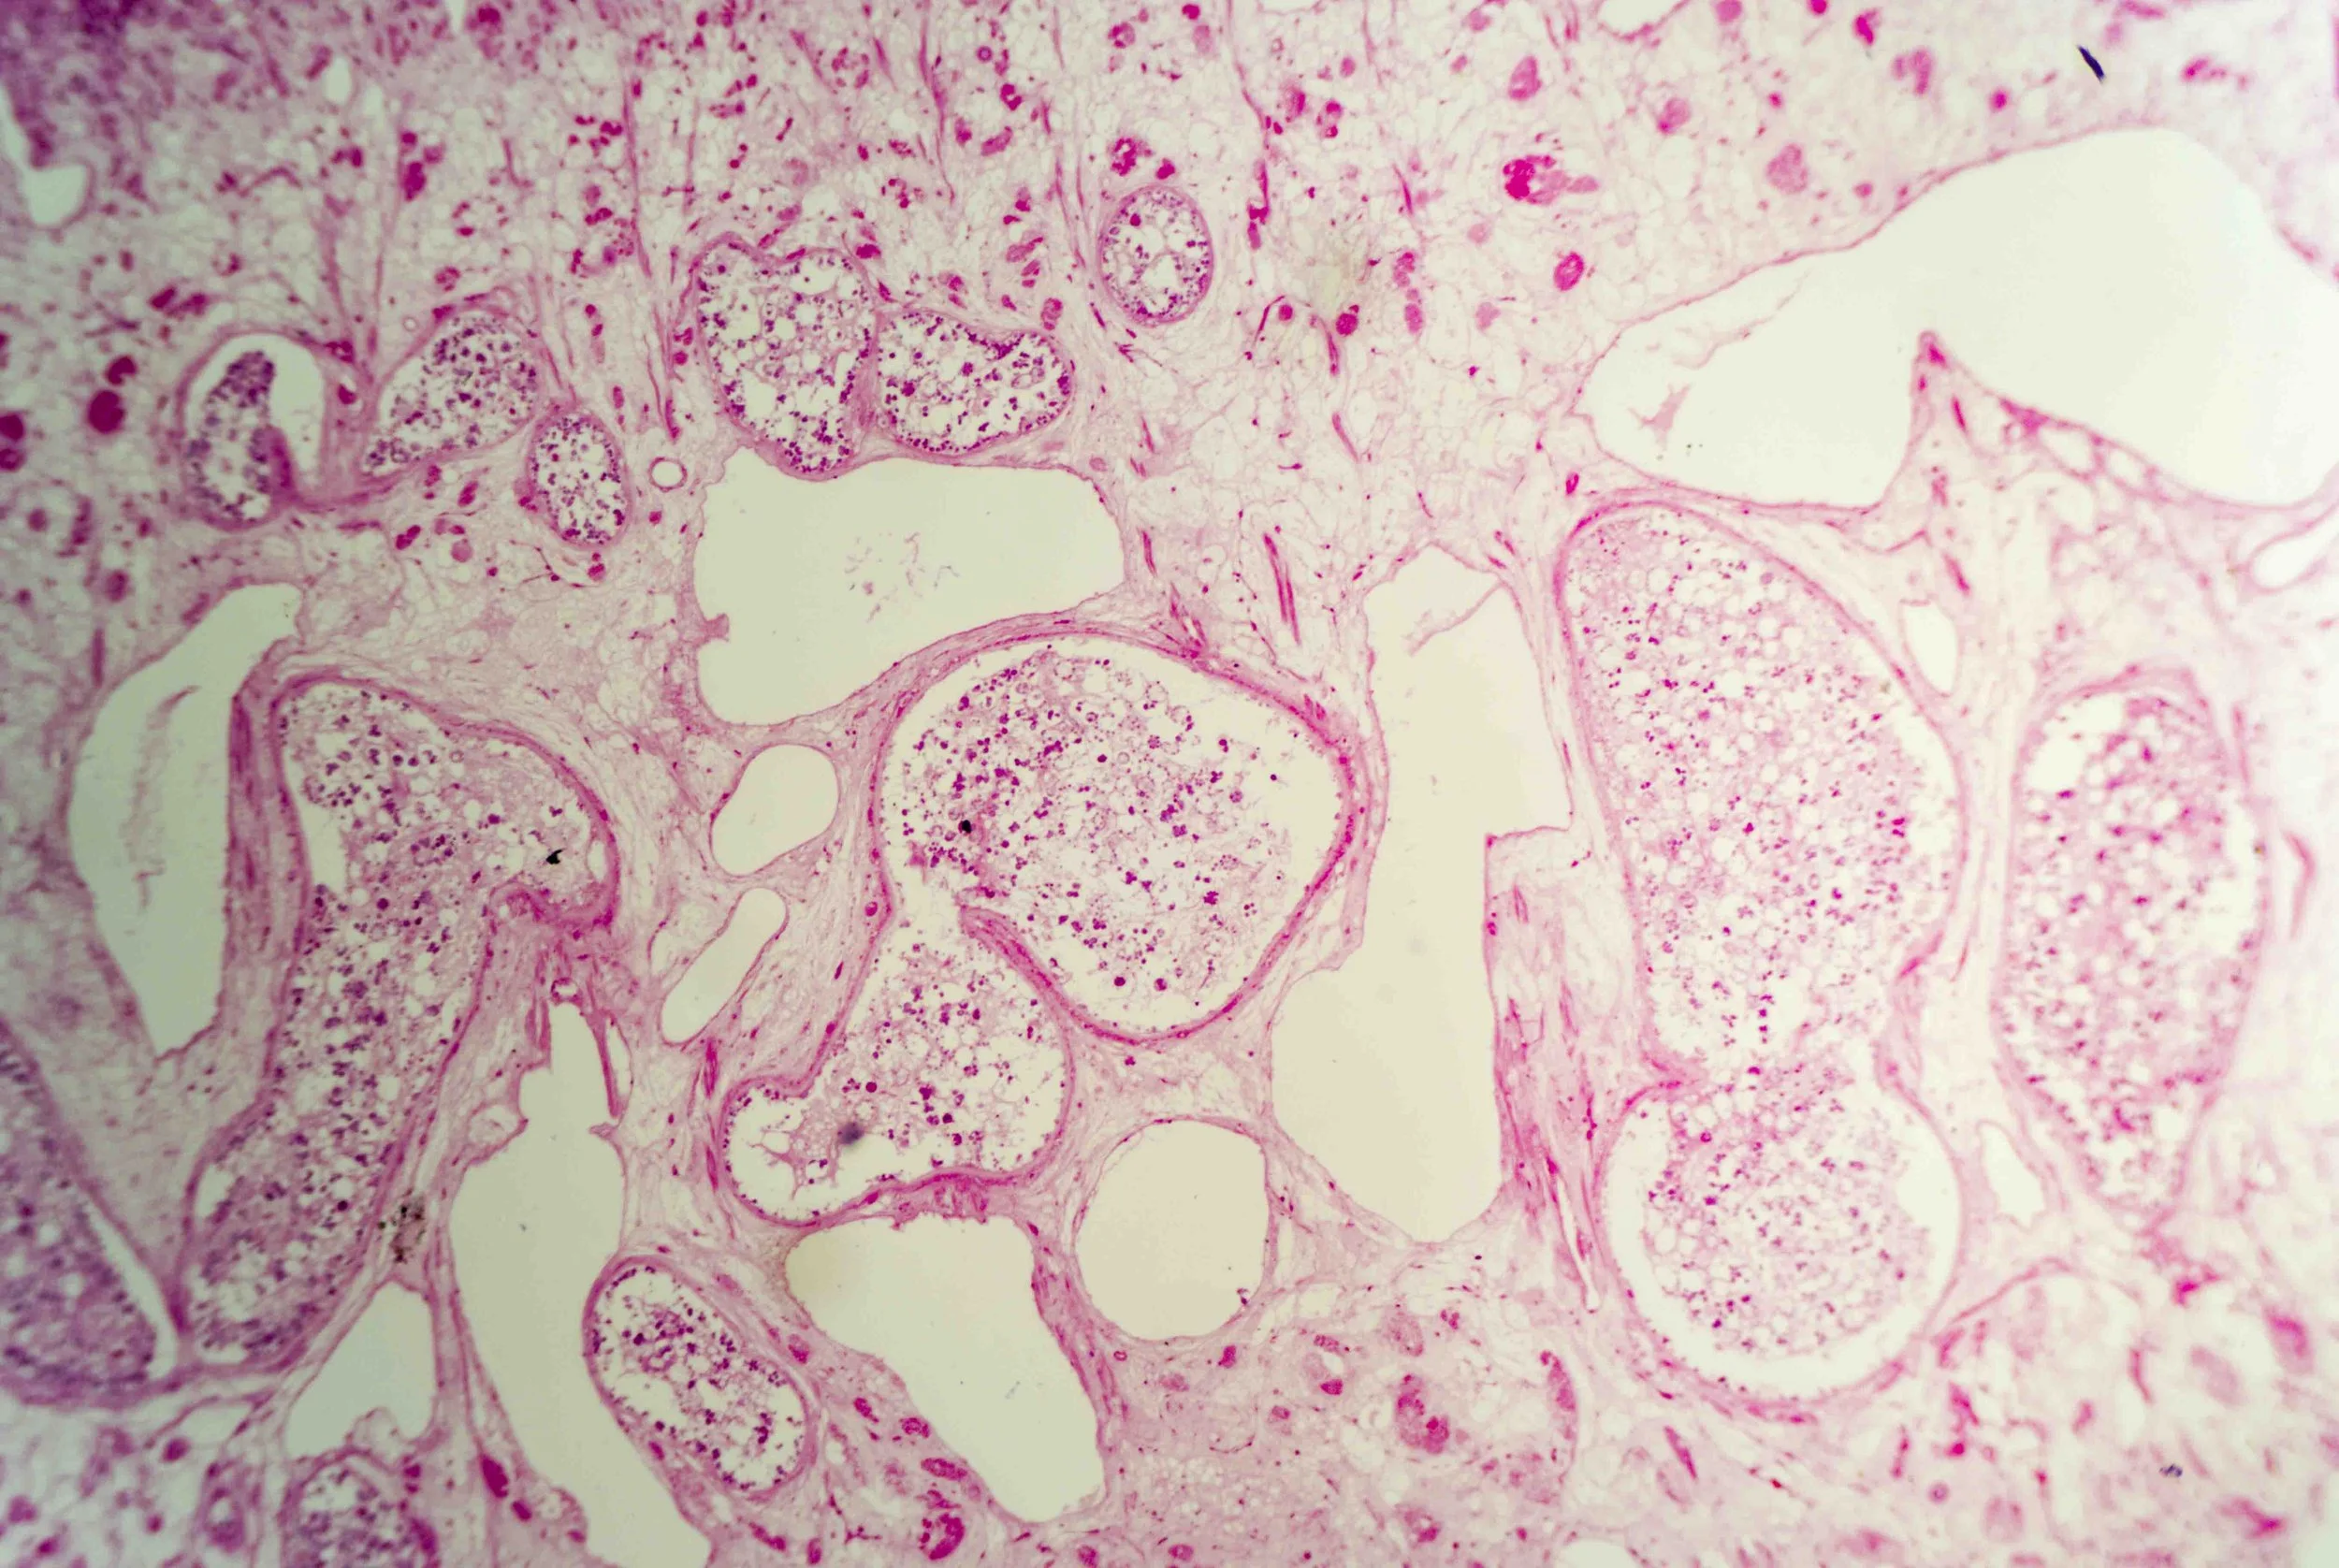

At first glance, a liver fluke is a simple, leaf‑shaped flatworm. Under magnification, however, a cross‑section reveals a labyrinth of chambers and cells, like stained‑glass windows filled with pink and purple mosaics. These sections show the parasite’s densely packed tissues, reproductive organs and digestive sacs nestled within its protective tegument.

The anterior end forms a conical “head” bearing a small yet powerful oral sucker used for feeding and adhesion. Just behind it lies a larger ventral sucker (acetabulum) that anchors the fluke to its host’s tissues.

The surface of the fluke is wrapped in a syncytial tegument—a scleroprotein‑rich skin enveloped in glycocalyx—that protects the parasite from digestive enzymes and allows nutrient absorption.

Liver flukes are hermaphrodites, carrying both male and female reproductive organs. They feed primarily on blood within the host’s liver and bile ductsen.wikipedia.org, and their branched intestine distributes nutrients throughout the body.

Yet there is an eerie beauty in their design. The intricate patterns seen in histological sections hint at the fluke’s complex adaptations—suckers, tegument, branched gut and prolific reproductive tissues—all evolved to exploit its ecological niche.